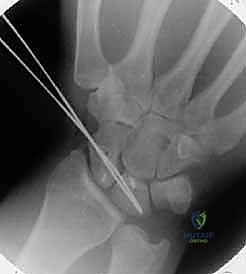

With the carpus stabilized, we can now prepare for graft insertion.

Tunnel Planning: We need to create bone tunnels in the scaphoid and lunate to accommodate the bone blocks of our graft.

- Using a small burr or a K-wire followed by a cannulated drill, create a tunnel in the scaphoid, entering dorsally and exiting volarly at the site of the original scapholunate ligament attachment.

- Similarly, create a tunnel in the lunate, entering dorsally and exiting volarly at its scapholunate attachment site.

- The tunnels should be sized to allow for a snug fit of the 10x5x5 mm bone blocks.

- Ensure the tunnels are positioned anatomically to recreate the natural course of the scapholunate ligament, particularly the strong dorsal component.

Surgical Warning: Drill under constant fluoroscopic guidance to prevent inadvertent penetration of the articular cartilage or neurovascular structures. The goal is to create tunnels that precisely mimic the anatomical footprint of the original ligament. Avoid creating tunnels that are too wide, as this will compromise bone block purchase.

TECH FIG 3 • B. Bone tunnels are created in the scaphoid and lunate to accept the bone blocks.